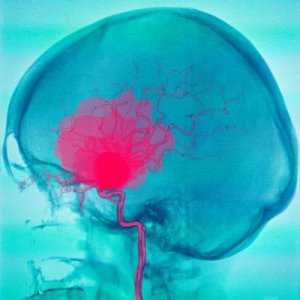

Opona twarda i opona pajęcza to dwie z trzech opon mózgowych, które ma człowiek. Opony są strukturami, które wyścielają centralny układ nerwowy. Krwotok podtwardówkowy lub podpajęczynówkowy odnosi się do poszczególnego krwotoku, który występuje poniżej każdej z tych dwóch opon.

W krwotoku podtwardówkowym lub podpajęczynówkowym pierwszą okolicznością jest odpływ krwi z naczyń krwionośnych. W konsekwencji krew zatrzymuje się i kumuluje przestrzeniach między oponami. Powoduje to następnie uszkodzenie tkanki mózgowej, generując różne objawy kliniczne.

Krwotok podpajęczynówkowy

Krwotok podpajęczynówkowy definiuje się jako gromadzenie się krwi między oponą pajęczą a oponą twardą. Krew jest zwykle pochodzenia tętniczego i powstaje z różnych przyczyn. Najczęstszą jest pęknięcie tętniaka, ale mogą go również spowodować pewne wady naczyniowe.